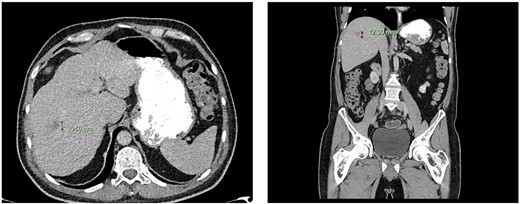

Computed tomography dated 12 March 2013 of the abdomen and pelvis measuring 8.70 mm (anterior–posterior) lesion at liver segment 5/6 in axial (left) and coronal (right) view.

Subsequent surveillance imaging including magnetic resonance imaging and CT scans demonstrated gradual reduction and eventual complete resolution of the liver metastases (refer to Figs 1–4). Furthermore, routine colonoscopy and a positron emission tomography (PET) scan revealed no evidence of locoregional cancer recurrence nor distant metastatic disease present; essentially rendering the patient cured from an initial diagnosis of metastatic rectal cancer. It has been at least a decade since his initial diagnosis and the patient remains in remission.

Following discussion within a multidisciplinary team, the patient underwent an uncomplicated palliative open Hartmann’s procedure in December 2012 for ypT3N1M1 upper rectal adenocarcinoma (1 out of 14 involved lymph nodes, immunoperoxidase staining of the tumour was negative for CK7, CK28 and CD18). Post-operatively, the patient opted for no further chemoradiotherapy and was also not deemed for surgical intervention regarding the liver metastases.